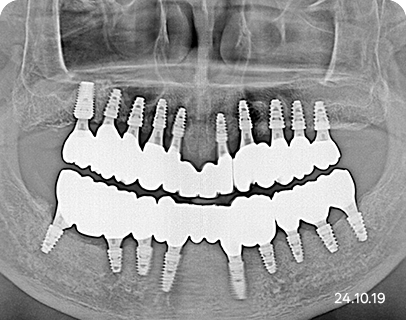

전체 임플란트 식립 예시

최대 식립 | 총 19개

절충형 식립 | 총 14개

최소 식립 | 총 12개

세종스타치과는 꼭 필요한 자리에만, 꼭 필요한 개수로 전체 임플란트 식립 치료를 진행합니다.